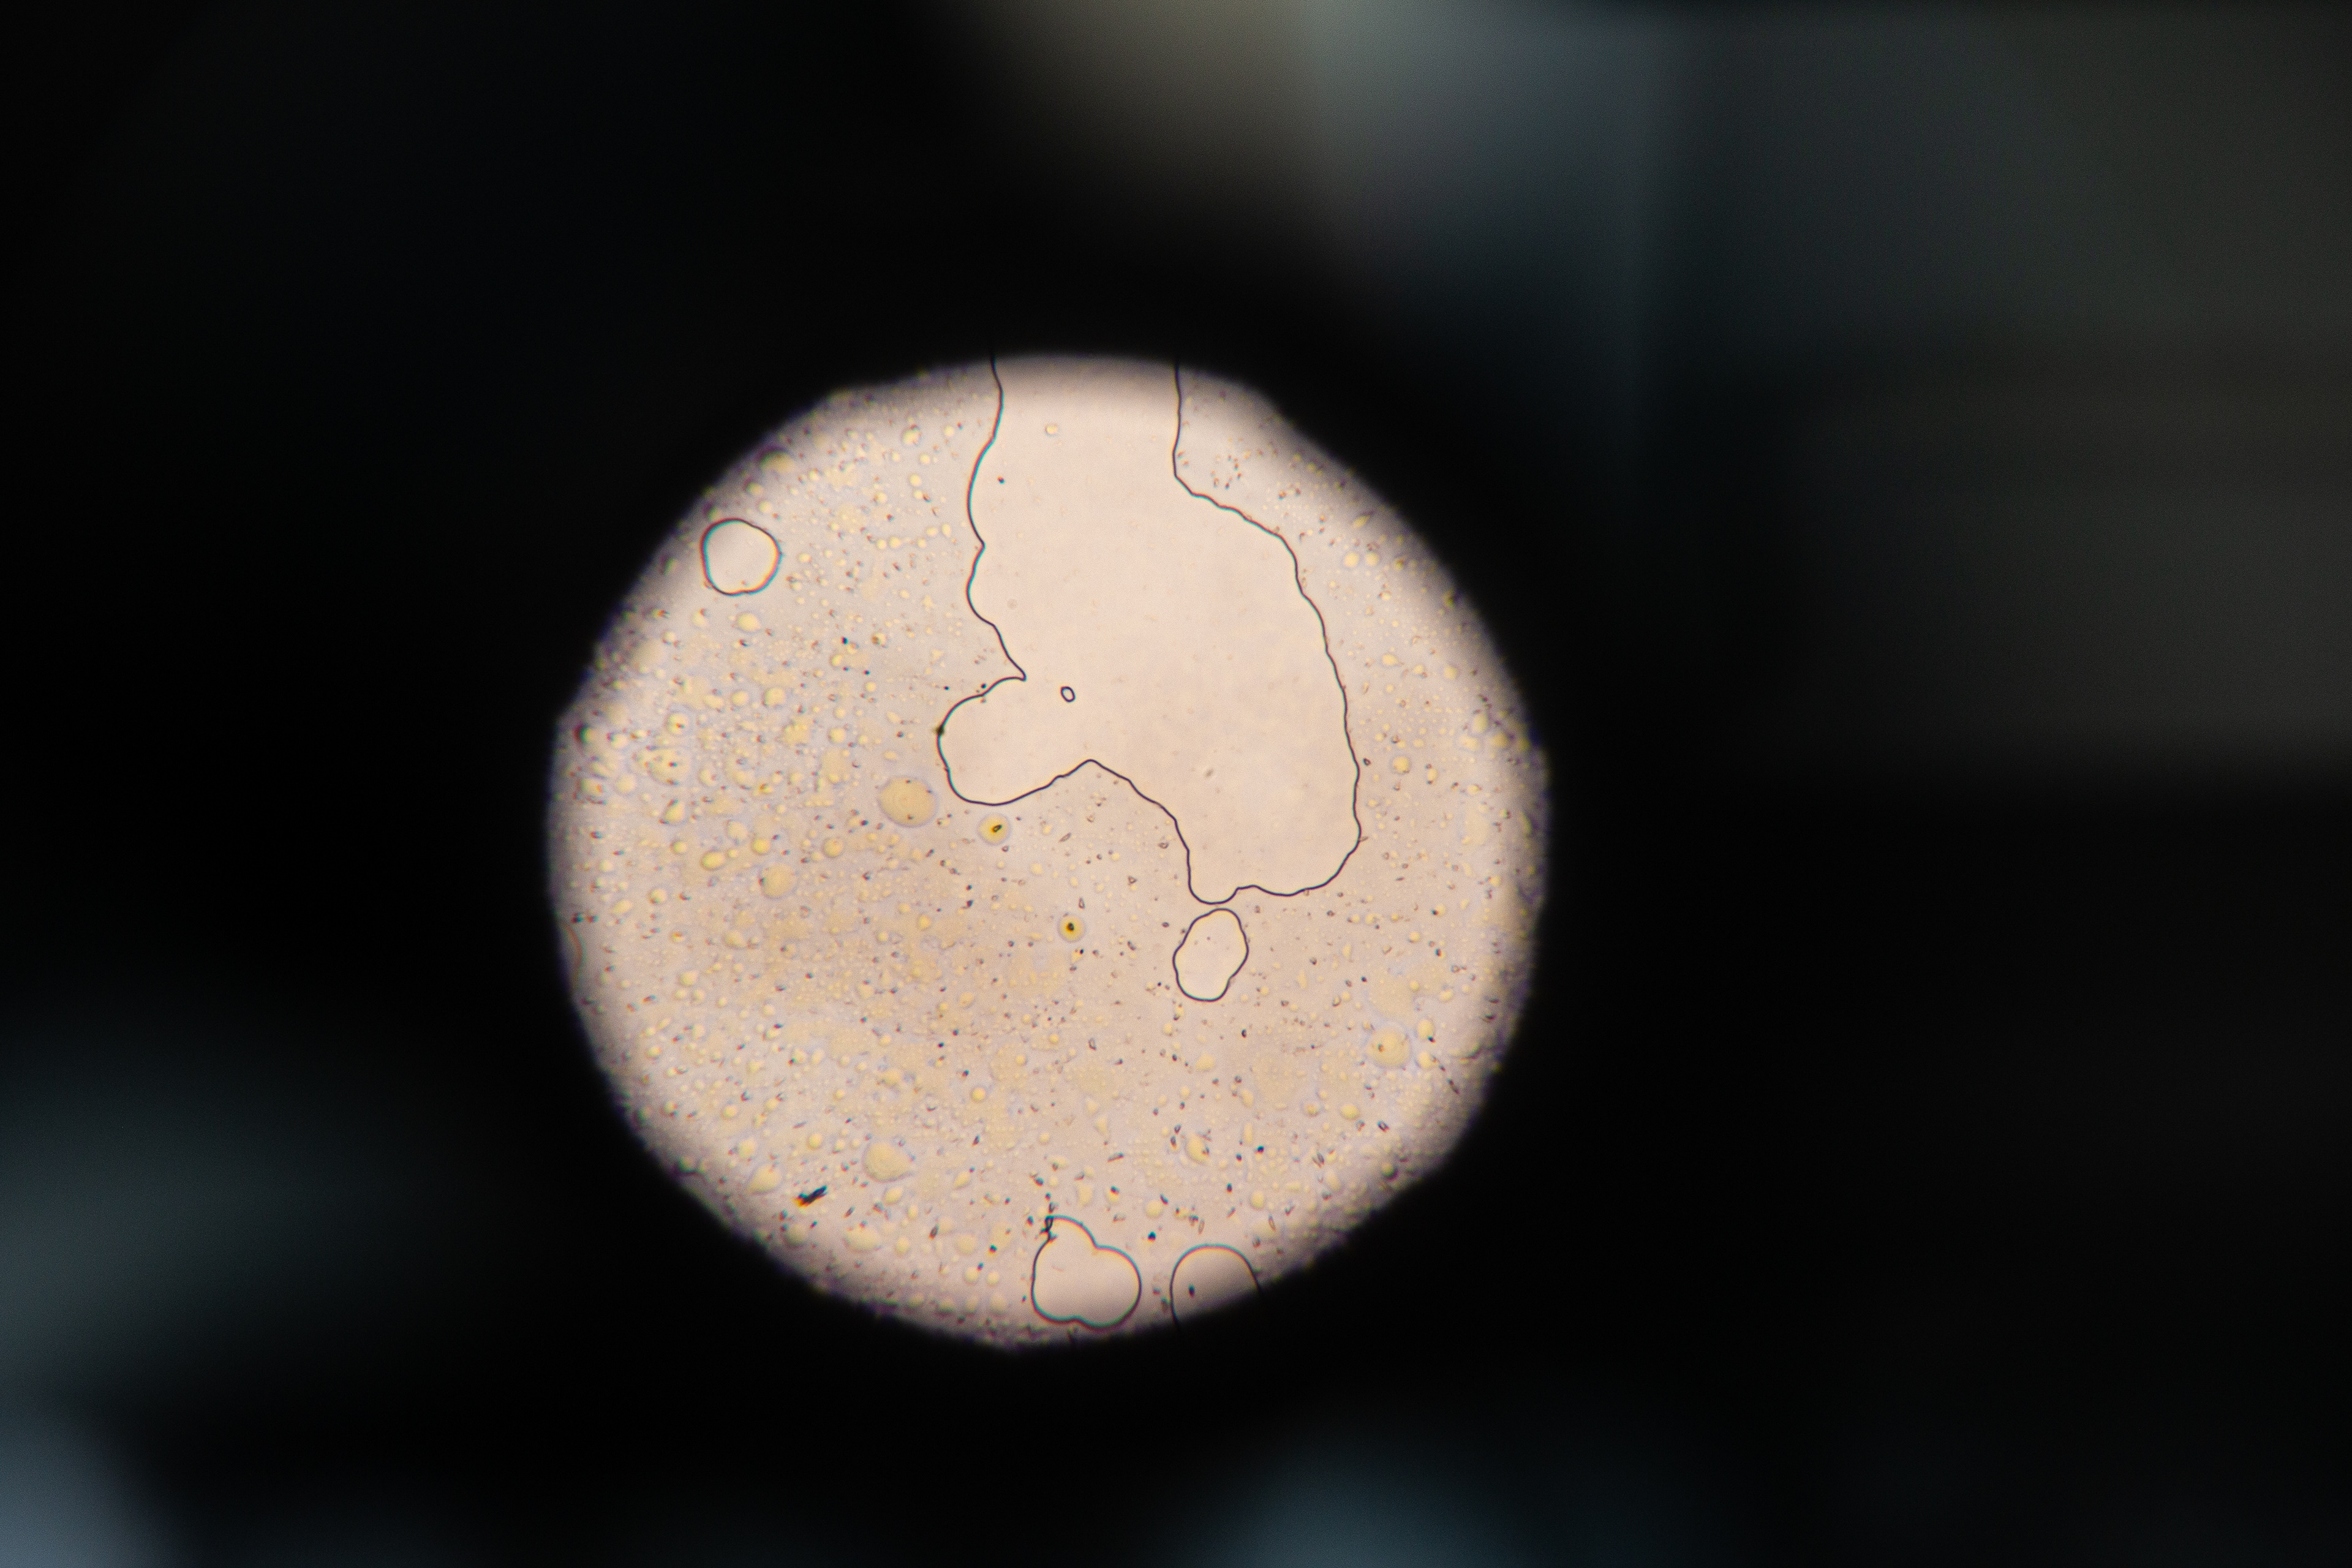

This got me curious. So, I collected and analyzed my own menstrual blood. First I took a look at my venous blood from my small finger and then compared it to my menstrual blood. The following pictures show my menstrual blood at different magnifications:

Menstrual Blood 40x